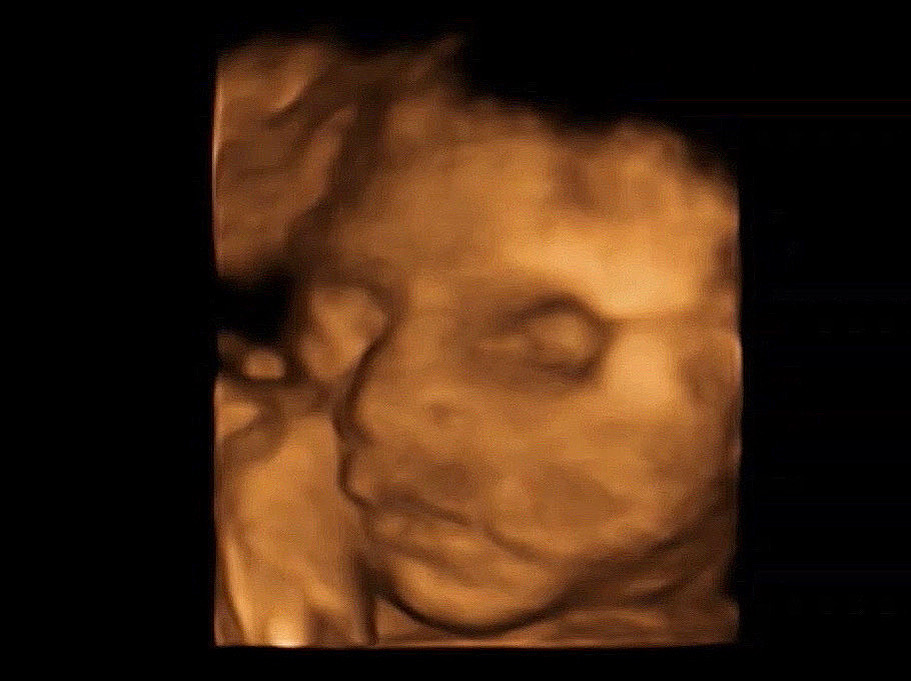

24wのエコー☺️

24wのときのエコーも載せちゃお😎 こう見ると29週になると脂肪も増えたのかぷくぷくして可愛い💗

お鼻がすごい高い子ですね!可愛いです〜🥺

嬉しいです🥹この1ヶ月後のエコーでは鼻にも脂肪ついた感じがありました😂🤍